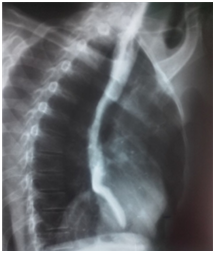

Mr T.A, aged 46, living in Bangui (Central African Republic) is consulted to emergencies for recurrent epigastric pain and dysphagia lasting for five months in a slimming context. This patient has a history of chronic alcohol abuse. He presented the clinical examination, impaired general condition (8kg / 5 months), a lack of palpable mass in the abdomen. In exploring this pain, abdominal ultrasound showed diffuse punctate calcifications in the entire pancreas, normal pancreatic duct, cystic mass in finely particulate content, lobulated epigastric 103mmde of major axis in cross section. It rises towards the tail of the pancreas and comes in contact with the heart. This mass was a very individualized wall without color Doppler signal. Chest X-ray showed fluid density mass, homogeneous, regular contours, retro heart (middle mediastinum, lower floor). A Transit oesogastro ulcer (UGI) Additional eliminated the presence of a mega-esophagus, a hiatal hernia or any training in communication with the digestive tract. Faced with increases in serum amylase and urinary amylase, the diagnosis of pancreatic cyst nickname to médiatisnale extension (mediation Lower-middle floor) on chronic pancreatic calcifying stigma was mentioned.

Figure 2 TOGD: Cardiac retro mass with mass effect on the esophageal bottom without communication with it (esophagus).